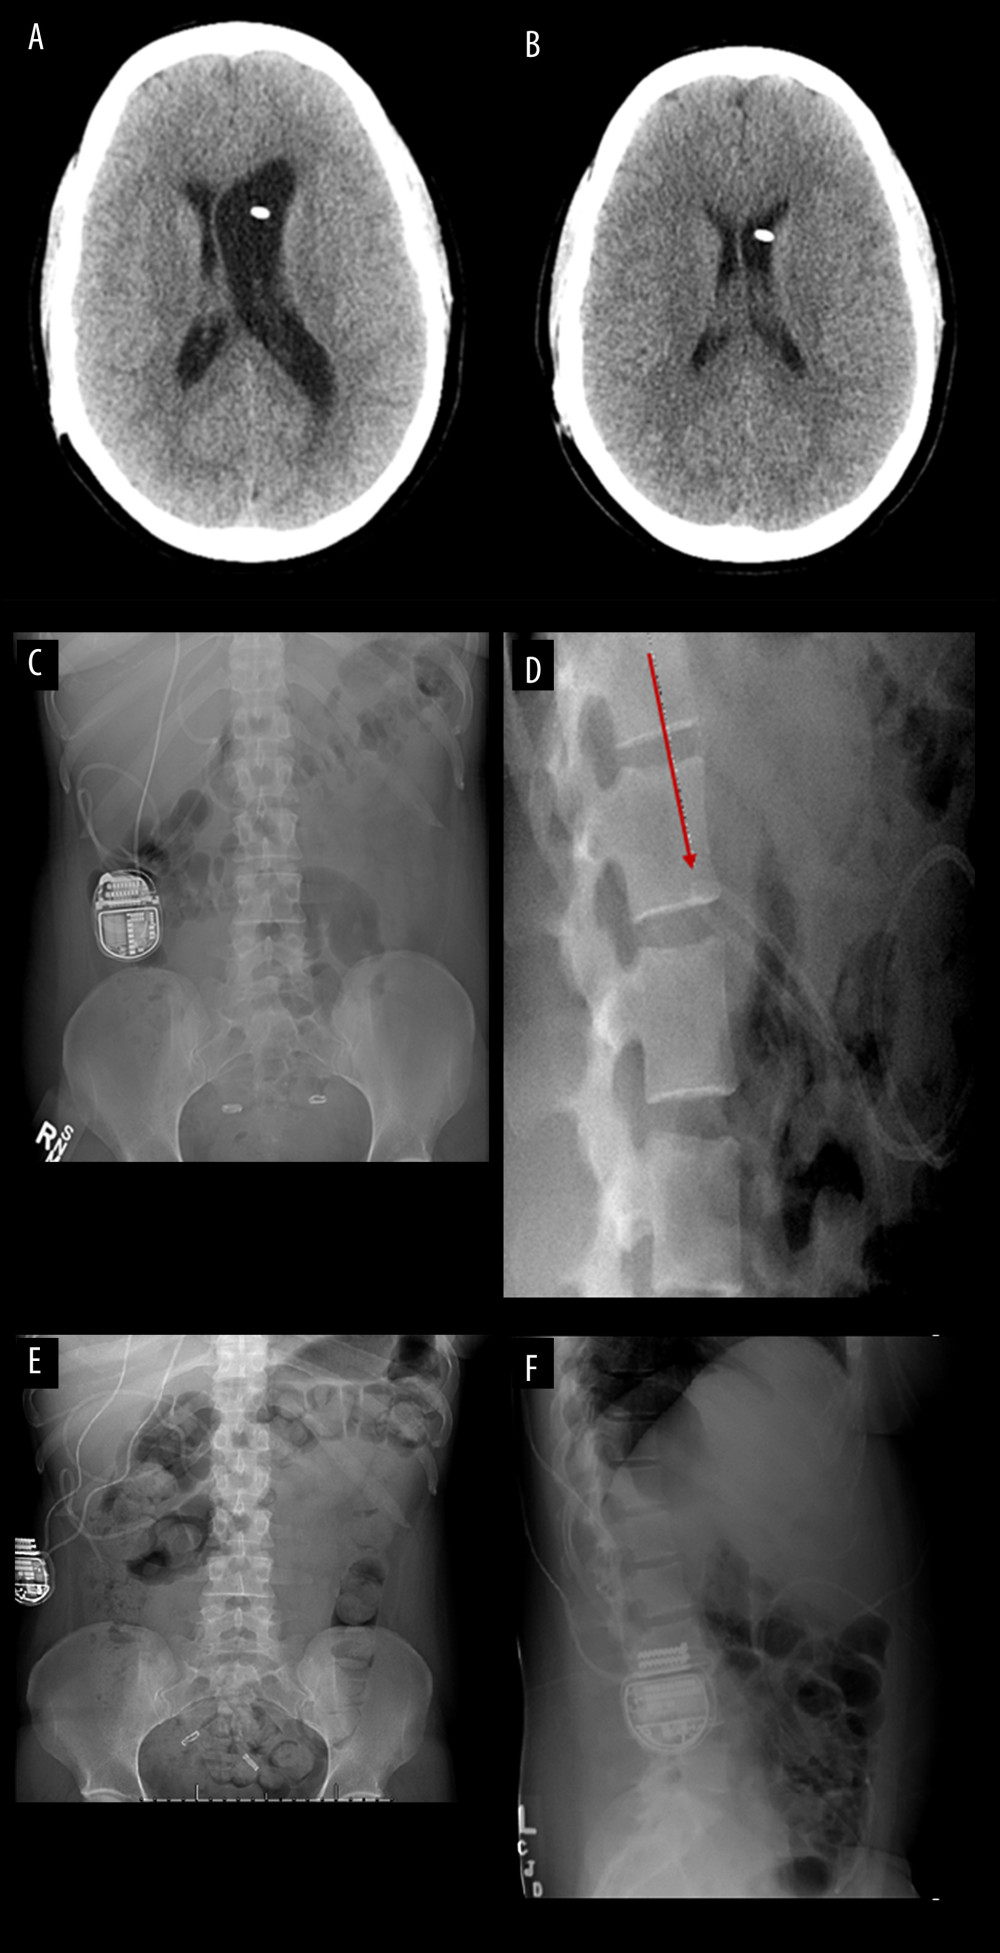

Tubal Ligation X Ray. Refer to the article on medical devices in the abdomen and pelvis for a view. It is a permanent form of birth control. Laparoscopic bilateral tubal ligation is a surgical procedure to occlude the fallopian tubes, which prevents pregnancy. They commonly fall off the fallopian tubes and move around in the. These large metallic staples are commonly seen in abdominal radiographs and are typical of tubal ligation clips. There are different methods of. Surgical clips used in laparoscopic tubal ligation procedures. When placed across the isthmic portion of the fallopian tube, tubal ligation clips serve as a means of rapid and effective tubal occlusion. Patients at high risk for. Knowledge of what to expect in a patient who has undergone uterine and fallopian tube interventions, such as uterine ablation and fallopian tube ligation, and of the potential associated complications (eg, postablation sterilization syndrome) also is pertinent. On mdct, the metallic clips are identified as small hyperdense cylindric structures or as solid circular structures close to the body of the uterus. This technique may be reserved as an initial screening test to evaluate the uterine cavity and test tubal patency.